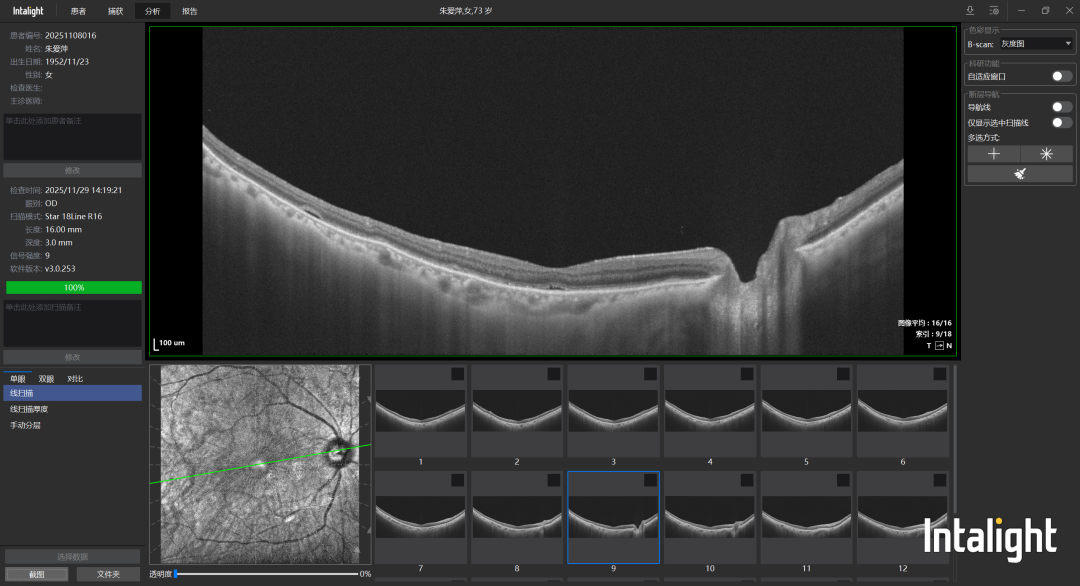

(高度近视性视网膜脉络膜病变)中老年人:定期进行眼部体检,尤其有高血压、糖尿病等基础病的人,需同时控制原发病,减少眼部并发症风险;